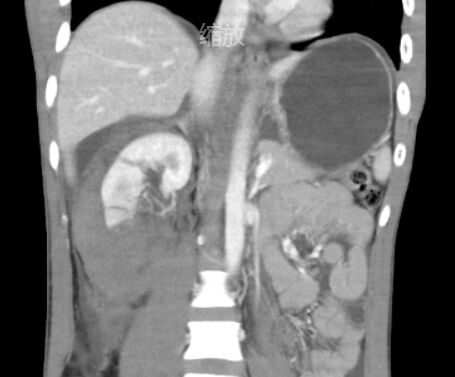

医生在术中先是清除了血肿和完全碎裂的部分肾组织,分层修复集合系统和肾裂口,尽可能保留正常肾组织。物理降温情况下阻断肾蒂约35min,完成血肿清除与肾组织的修复与缝合。术中出血少,术后生命体征平稳

小叶右肾术后CT图片

手术顺利完成,1周后,小叶复查了CT平扫,图片显示右肾仍保留超过2/3的体积,肾周血肿情况消失,小叶恢复顺利。“感谢庞主任团队!”小叶及其家属难掩心中的喜悦与感激之情。